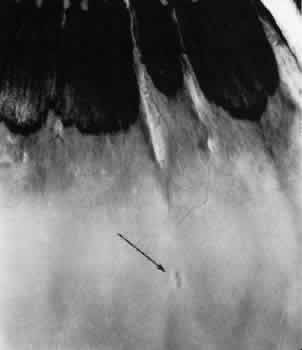

Fig. 9. Meridional complex (arrow). Note its basic constituent, an atypical dentate process, which aligns with and extends to an enlarged ciliary process. Complex also has a meridional fold which extends along the dentate process and posteriorly into the peripheral retina.

Fig. 10. Microsection of meridional complex through atypical dentate process and its meridional fold. Anteriorly (on the left) the complex shows marked redundancy of pigmented epithelium in its outer aspect and a dense glial plaque on its inner aspect. Posteriorly (on the right) there is microcystoid change, nonspecific degeneration, and dense-staining glial cells along its surface. (Hematoxylin-eosin; × 63.)

Meridional complexes are present in 16% of the population, are bilateral in 58% of affected patients, and thus are present in 12% of all eyes (see Table 2). The complexes are multiple in 45% of the affected eyes; they are most common in the superior nasal quadrant.